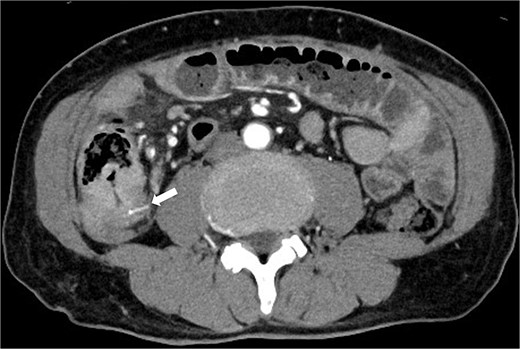

Three months prior, the patient presented with similar symptoms. CT revealed a high-density area in the same region that was thought to be a foreign body, identical to the foreign body seen on the preoperative CT, and circumferential wall thickening (Fig. 2). Although AFP was 1507 ng/ml consistent with 1400–1600 ng/ml, the findings of recurrence had not been detected in internal medicine follow-up. Ileal penetration, rather than perforation, caused by a foreign body was suspected. Since there were no peritoneal signs, conservative treatment was initiated, leading to temporary symptom relief.

CT taken 3 months before surgery revealed a high-density area in the small intestine of the right lower abdomen that was thought to be a foreign body identical to the foreign body seen on the preoperative CT scan, as well as circumferential wall thickening.